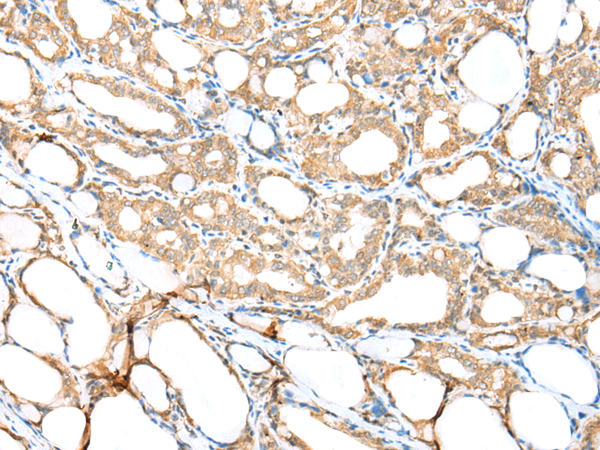

分类: 科研抗体货号: P02100别名:应用: WB,IHC反应种属: Human, Mouse

分类: 科研抗体货号: P02020别名: Ipi3; R32184_1应用: WB,IHC反应种属: Human, Mouse

分类: 科研抗体货号: P01920别名: HAT应用: WB,IHC反应种属: Human, Rat

分类: 科研抗体货号: P02094别名: EMC5; TMEM32应用: WB,IHC反应种属: Human, Mouse, Rat

分类: 科研抗体货号: P01915别名: CAPH2; MT-SP2; TMPRSS3应用: WB,IHC反应种属: Human, Mouse

分类: 科研抗体货号: P02005别名:应用: WB,IHC反应种属: Human, Mouse, Rat

分类: 科研抗体货号: P02092别名: NAAGS; FAM80B; NAAGS-I应用: IHC反应种属: Human, Mouse

分类: 科研抗体货号: P02085别名: ECO; ICK; MRK; LCK2; EJM10应用: IHC反应种属: Human, Mouse, Rat

分类: 科研抗体货号: P02002别名:应用: WB,IHC反应种属: Human, Mouse